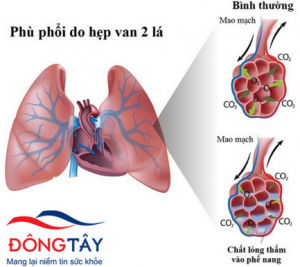

Định nghĩa:

- Phù phổi cấp là tình trạng dịch tràn từ mạch máu vào khoảng kẽ phế nang và vào lòng phế nang, tỉ lệ tử vong chiếm khoảng 15-20 %

Sinh lý bình thường:

- Dịch chỉ có trong mạch máu, không tràn vào kẽ và lòng phế nang

- Nguyên nhân do màng phế nang khong thấm nước

- Dịch chỉ di chuyển vào khoảng xung quanh mạch máu phế quản

- Lượng dịch vào khoảng kẽ được hệ bạch huyết thu hồi lại vào đại tuần hoàn

- Áp lực thủy tĩnh của mao mạch phổi tăng lên:

Dịch trong lòng mạch thoát khỏi màng phế nang vào trong lòng phế nang

Dịch trong lòng phế nang không mang theo được protein nên gọi là “ dịch nghèo protein”

- Khi tăng tính thấm thành mạch phổi thì tăng lượng dịch và protein đi vào kẽ và lòng phế nang